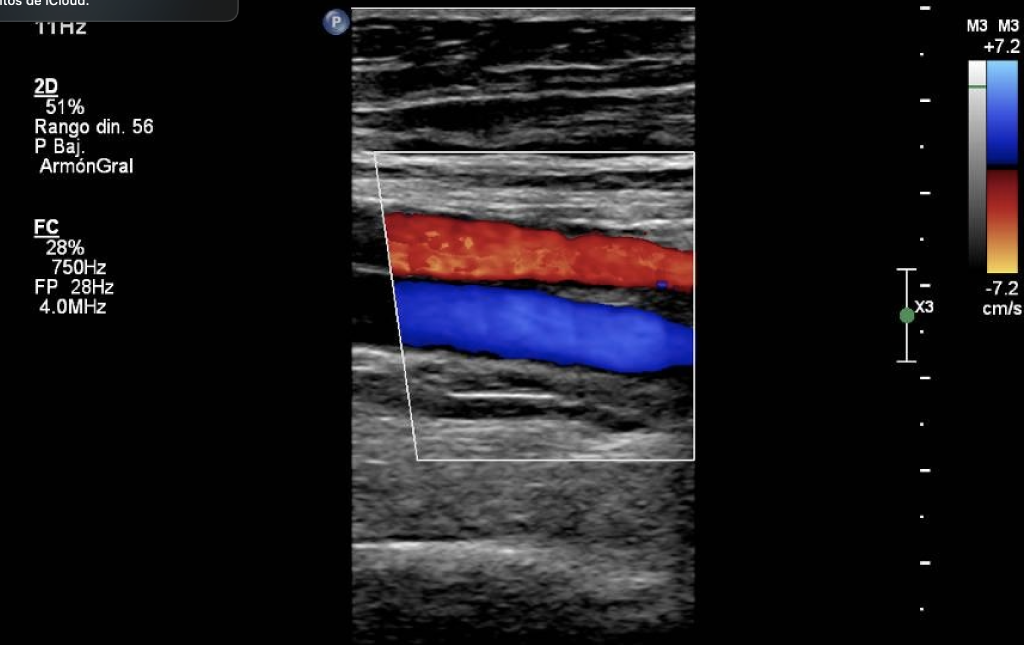

El Ultrasonido Especializado Doppler Vascular es recomendado para:

✅ Doppler Carotídeo y Vertebral